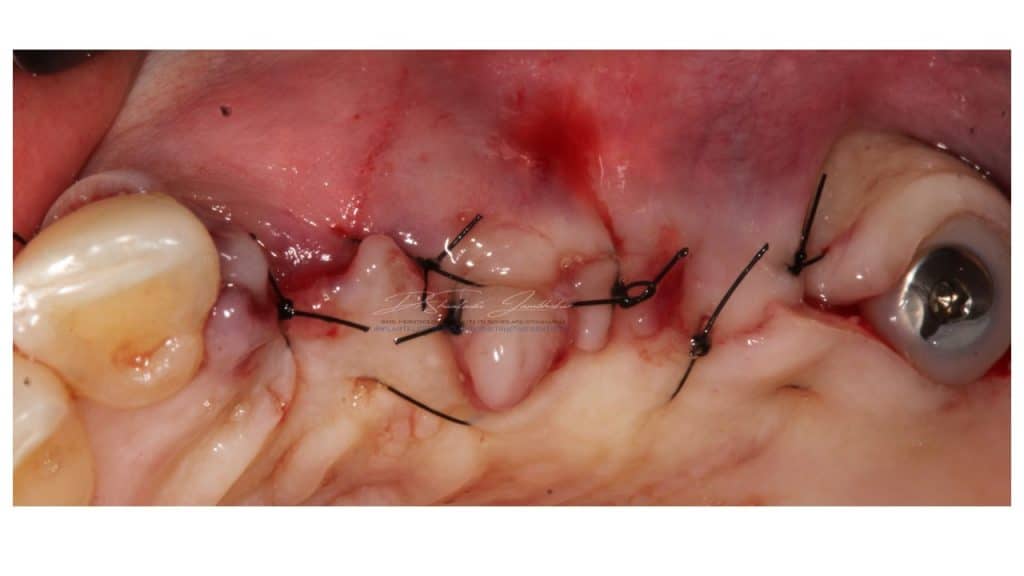

Primary closure with 5-0 Nylon sutures

Modified flap design for buccal soft tissue augmentation and custom healing abutment in situ